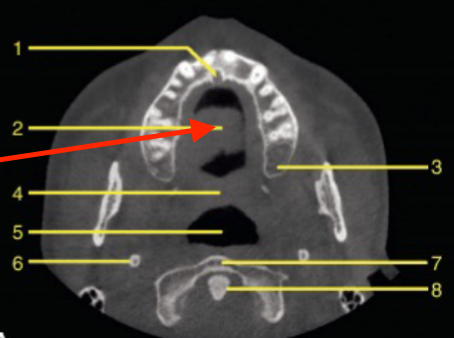

axial

what plane is this

beeam hardening (braces)

what is the cause of this artifact

mental foramen

what is the structure indicated by the arrow

submandibular fossa

identify 5

inferior alveolar canal

identify the structure